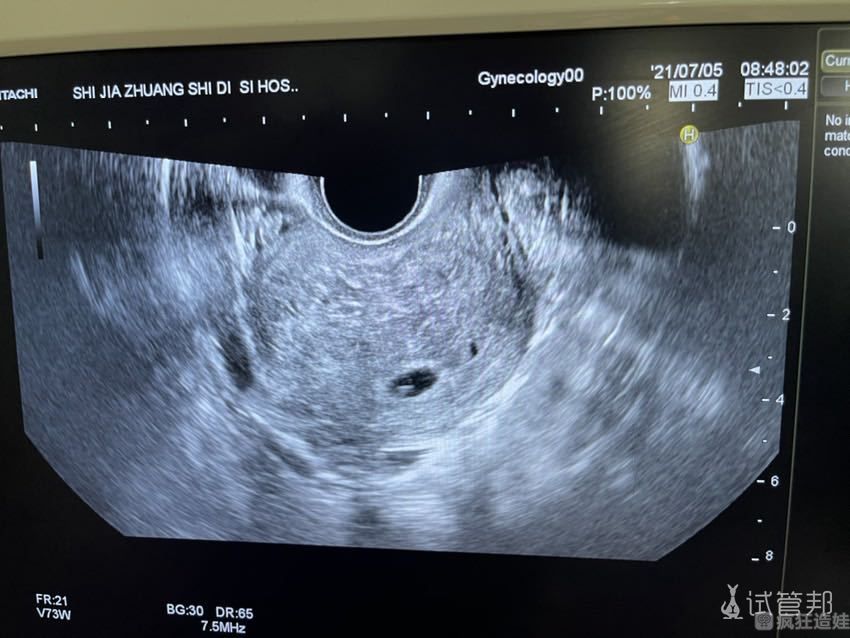

2021年6月11日。我去医院复查B超+激素,医生又开了2天针。2021年6月13日,再次去复查B超+激素,这次医生开了1支(乐宝得)尿促性素针(75iu)和2支绒促性素针(5000iu)。6月16日,一大早我们去医院做了取卵和取精。